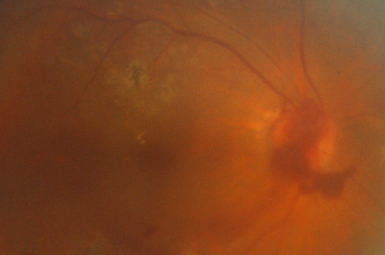

Retinal Detachment

This potentially blinding condition requires prompt surgical intervention. Successful reattachment usually preserves or restores visual function.

Image courtesy of Carl Zeiss Meditec, Inc.